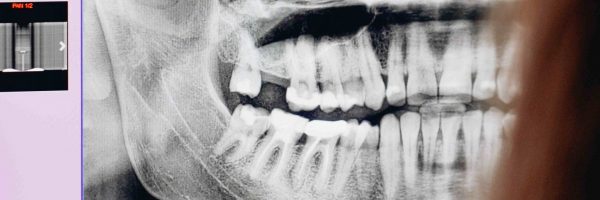

Radiografía dentadura

FASE 5

OBTURACIÓN

Se rellena el conducto radicular y se sella herméticamente para aislar el diente del resto del organismo. La técnica y los materiales utilizados se eligen según las necesidades específicas de cada caso.

Se requiere un seguimiento regular del tratamiento, que incluye controles clínicos y radiográficos para evaluar la evolución. La periodicidad de estos controles depende de la situación particular de cada paciente.